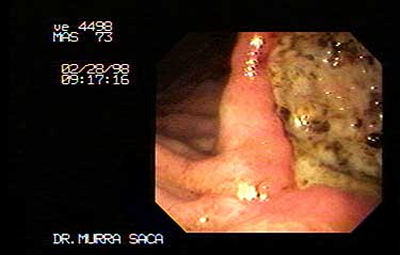

Paciente Masculino de 73 años:

Quien presenta adenocarcinoma ulcerado del antro e incisura angularis.